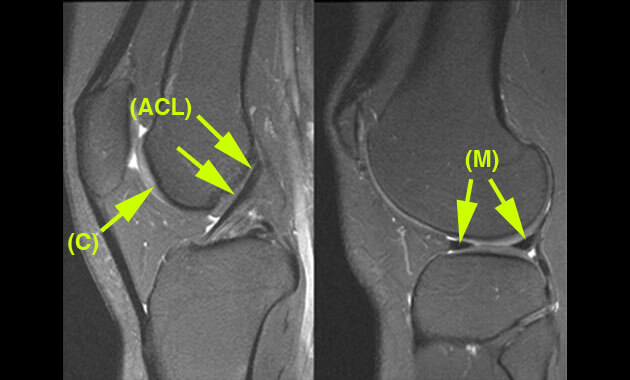

- ACL (Anterior Cruciate Ligament) Tear

- Osteoarthritis of the Knee

- Sports injuries